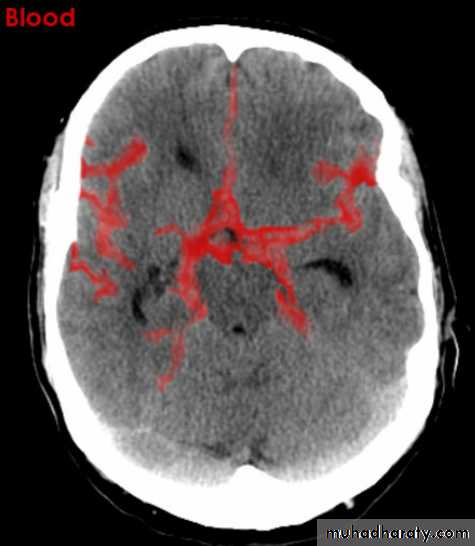

Subarachnoid hemorrhage

causesdue to ruptured aneurysm over 90 % of cases spcially at the circle of Willis .

ruptured AV malformation .

trauma .

CT finding

hyper density is seen within the SAS ( hyperdense sulci , being filled with clotted blood)

opacified inter hemispheric fissure ( become white & more dense )

opacification of the falx cerebri .

SAH

White sulciOpacified IHF